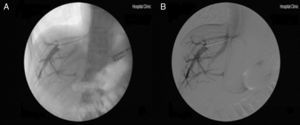

La práctica de un estudio hemodinámico hepático y/o la elastografía hepática pueden dar datos muy útiles de sospecha de HPINC. Así, los pacientes con HPINC presentan una alta incidencia de comunicantes vena-vena en el cateterismo de venas suprahepáticas (que en muchas ocasiones dificultan lograr una correcta oclusión de la vena suprahepática) (fig. 2) e, incluso si se logra una adecuada oclusión, el gradiente de presión venosa hepática es habitualmente normal o está sólo discretamente elevado, muy por debajo de lo esperado en un paciente con cirrosis hepática y signos semejantes de HTP, infraestimando la verdadera presión portal que presentan10,22,64,65. Ello se debe fundamentalmente al aumento de la resistencia intrahepática a nivel presinusoidal66,67. De forma semejante, los pacientes con HPINC presentan valores usualmente elevados en la elastografía hepática de transición (Fibroscan®) pero claramente inferiores a los valores descritos en pacientes con cirrosis hepática22,68. Raramente los pacientes con HPINC presentan valores superiores a 12kPa22,65. Ante un paciente con signos claros de HTP, estos hallazgos en el GPVH y en el Fibroscan nos deberían hacer sospechar la presencia de una HPINC. Un estudio reciente utilizando acoustic radiation force impulse (ARFI); una técnica ecográfica que también mide la rigidez hepática de forma no invasiva sugiere que el hallazgo de una razón rigidez del bazo/hígado ≥1,71, tendría una gran capacidad diagnóstica para diferenciar los pacientes con HPINC de los pacientes con cirrosis hepática y hepatitis crónica69. Se están evaluando otros métodos no invasivos para ayudar a establecer el diagnóstico de HPINC. Datos preliminares sugieren que los pacientes con HPINC presentan un perfil metabolómico sérico diferencial (que incluye entre 3 y 5 metabolitos) cuya determinación podría permitir el diagnóstico especifico positivo de esta entidad70. También se ha sugerido que el estudio del patrón de perfusión hepática mediante ultrasonografía con contraste71 o el hallazgo de niveles séricos de vitamina B12≤250pg/ml72 podrían permitir la diferenciación entre HPINC y cirrosis hepática criptogénica. No existen estudios en la actualidad que hayan validado estos hallazgos en muestra amplias de pacientes.